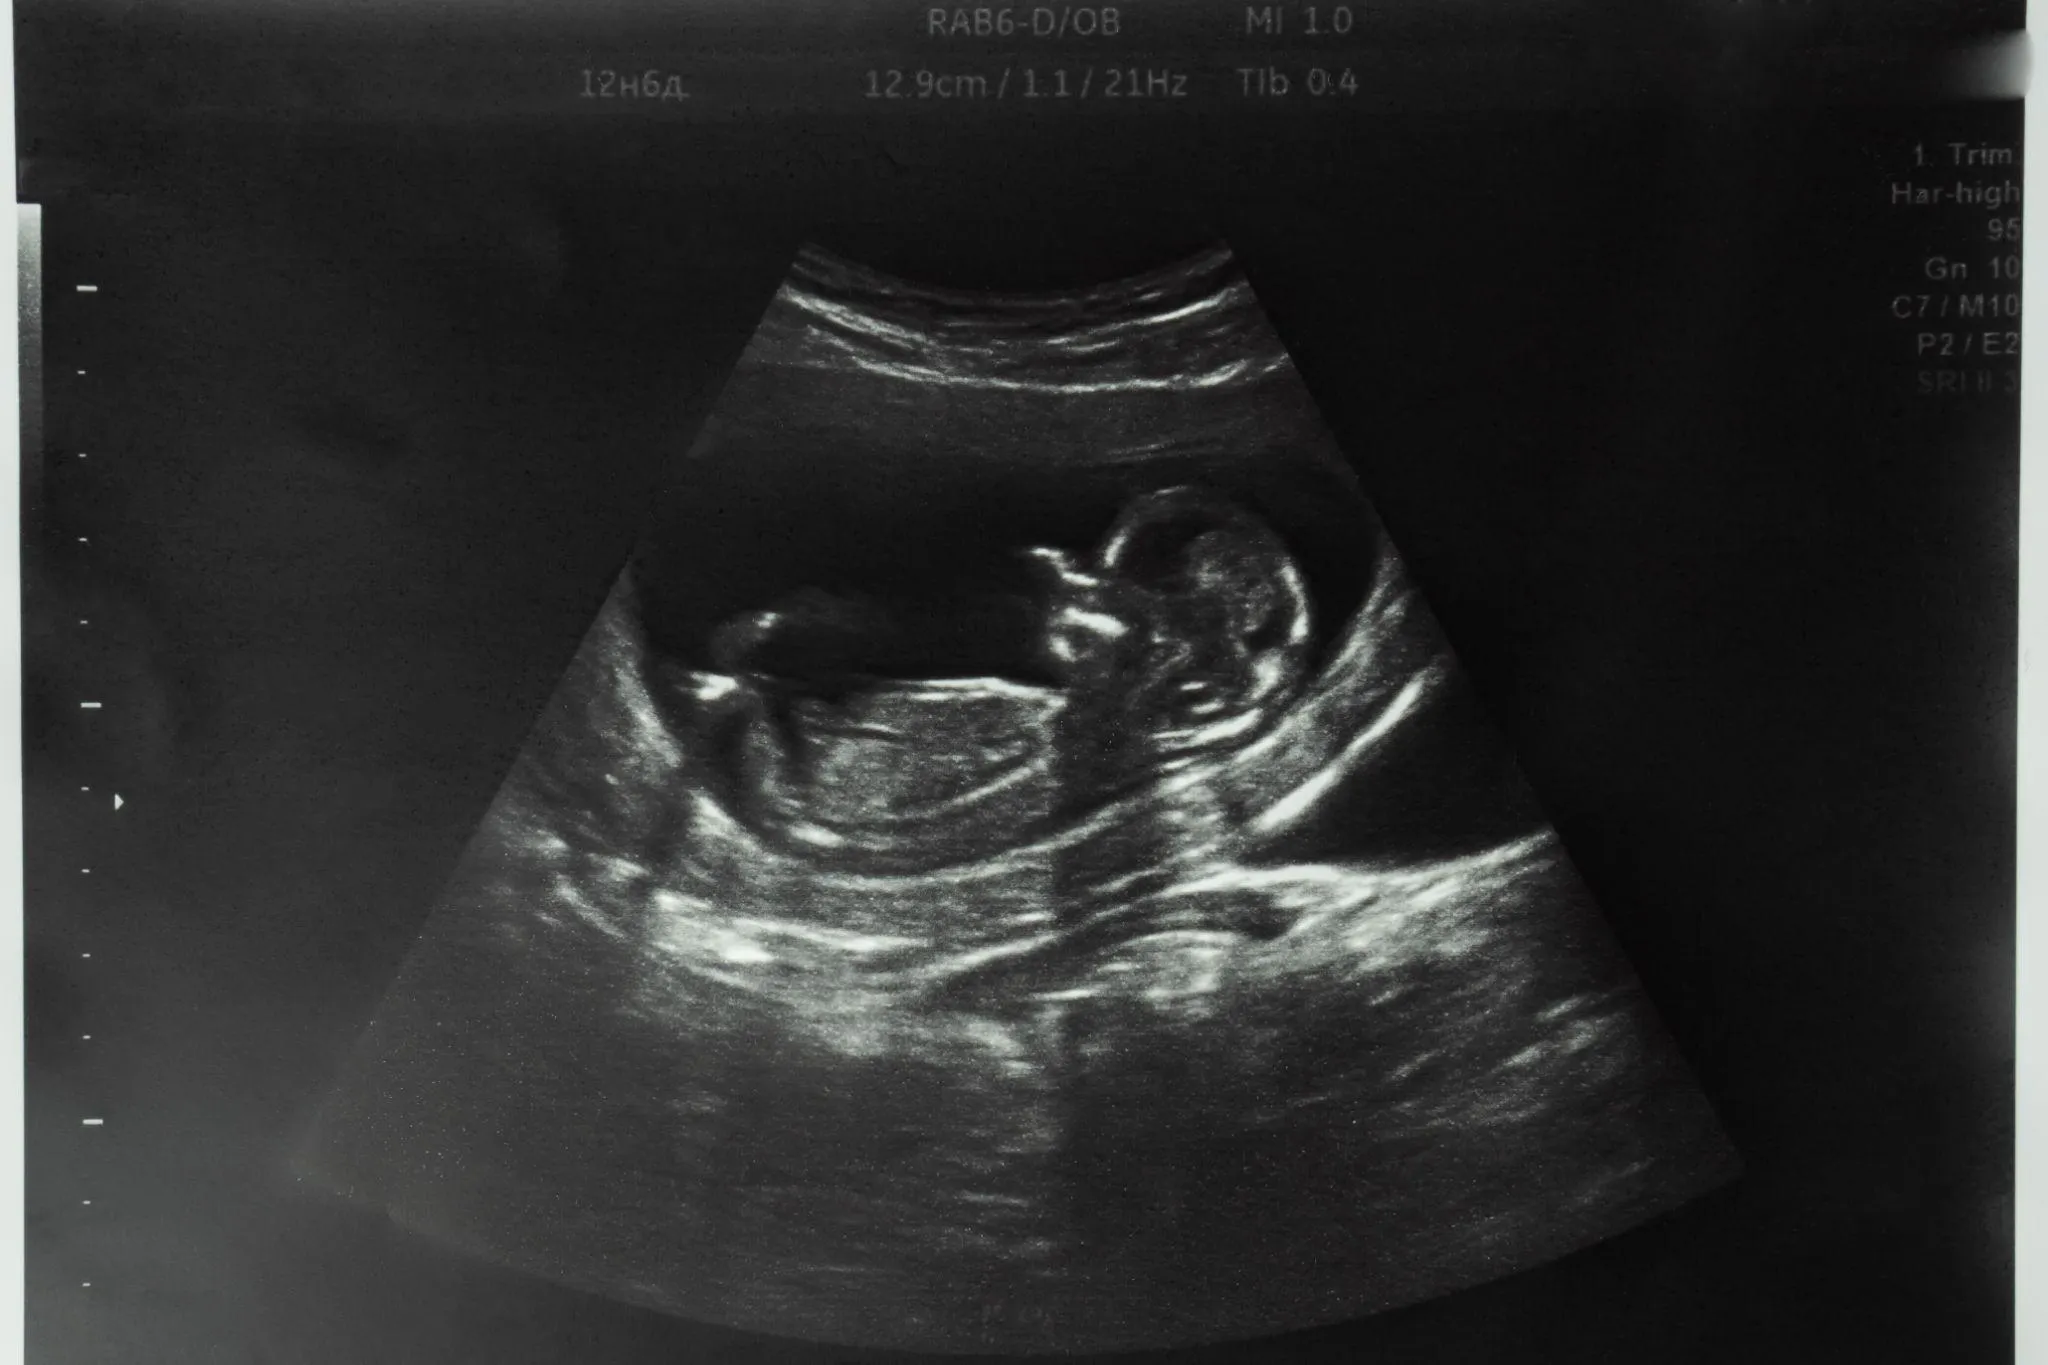

妊娠時期別のエコー写真の見方

エコー写真の見え方や確認すべきポイントは、妊娠週数によって異なります。ここでは、妊娠時期別に何をチェックしているのかを解説します。

妊娠12週頃からのチェックポイント

妊娠12週頃からは、お腹の上にゼリーを塗って測定する経腹エコーに移行します。赤ちゃんが大きくなり、お腹の上からでも確認できるようになるためです。

この時期には胎盤が完成し、羊水量も徐々に増えてきます。BPD(頭の横幅)、FL(太ももの骨の長さ)、AC(お腹周りの長さ)を測定して推定体重(EFW)を算出します。

また、心臓や脳、骨格などの臓器の構造に大きな異常がないかも確認します。